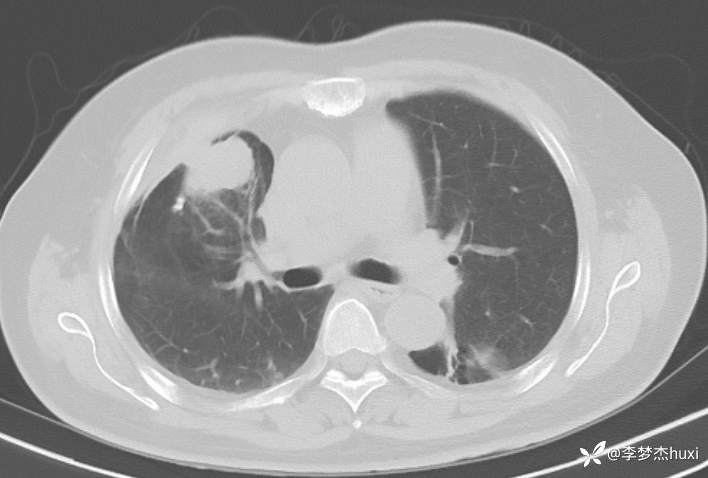

女性69岁,胸痛住院,检查发现肺占位性病变,猜病理

辅助检查:胸部CT:右肺占位?炎症?双肺炎性变,左肺下叶陈旧性病变,双肺纹理增多,主动脉及冠状动脉钙化,双侧胸膜局部增厚,胆囊结石,多发肝囊肿?请结合超声。

临床诊断:肺占位